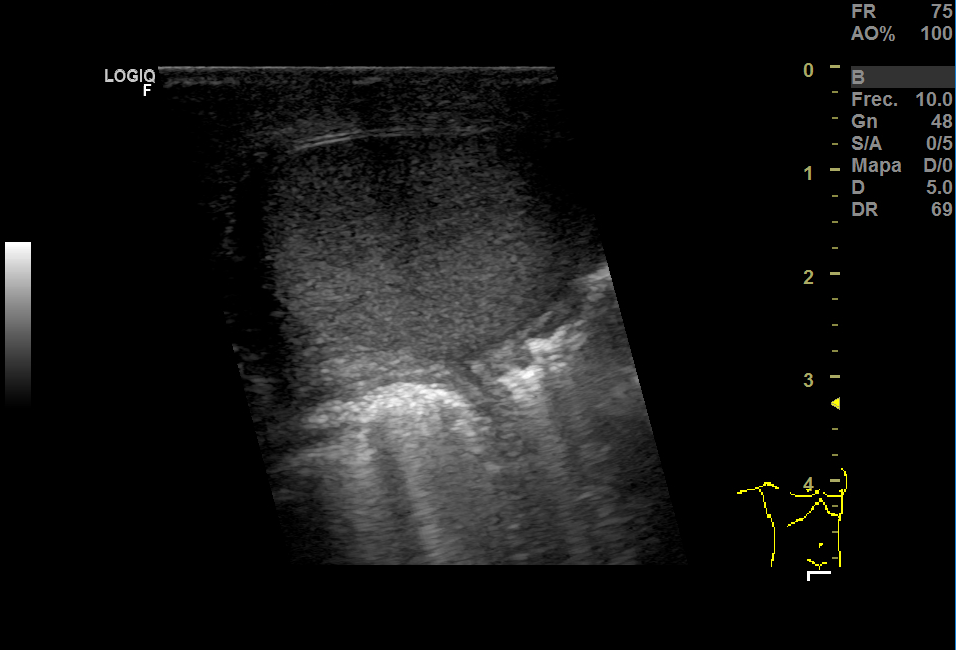

Realizamos una ecografía en Centro de Salud donde vimos que había una herniación derecha y aumento del grosor del tejido celular subcutáneo y, en el espesor, una imagen anecoica que no sabíamos bien a qué podía corresponder.

En la urgencia, realizaron una analítica y encontraron 14.600 leucocitos, PCR 5,13. En Eco testicular, se apreciaron testes de ecoestructura y ecogenicidad normales, epidídimos normales y aumento del grosor del TCSC que impresionaba de celulitis y, en el espesor, una pequeña colección de 15 mm que podía corresponder a absceso o hematoma.